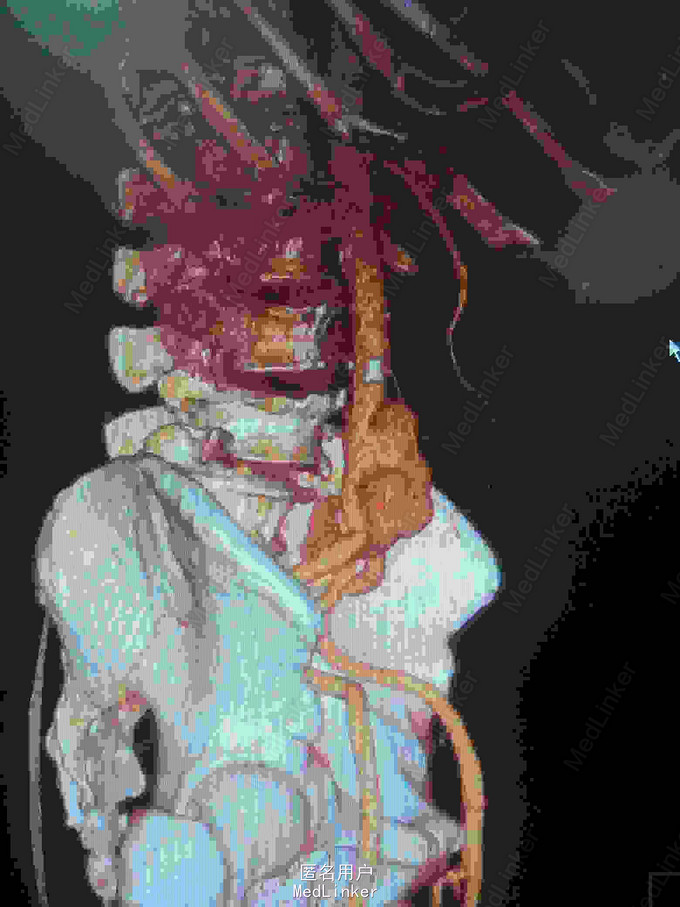

主诉:腰腹痛7月,加重一周。 病史:七月前发热后开始出现腰腹痛,呈持续性撕裂样痛,伴腹胀,症状反复。一周前腹痛症状加重。

体查:下腹部可触及搏动性包块。 辅助检查:腹部CT:腹主动脉假性动脉瘤并血栓形成,腰5椎体受侵蚀。血培养:沙门氏菌。

诊断:沙门氏菌感染性腹主动脉假性动脉瘤 处理:急诊行腹主动脉瘤切除人工血管置换术,术后予美罗培南抗感染8周,续以左氧氟沙星口服。